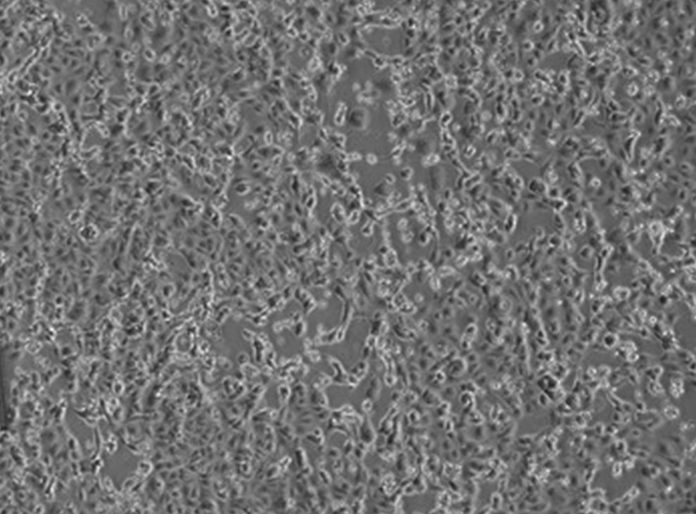

ROMA (ITALPRESS) – I virologi dell’Istituto Nazionale Malattie Infettive “Lazzaro Spallanzani”, a meno di 48 ore dalla diagnosi di positività per i primi due pazienti in Italia, sono riusciti, primi in Europa, a isolare il virus responsabile dell’infezione. Avere a disposizione il virus è un passo fondamentale che permetterà di perfezionare i metodi diagnostici esistenti ed allestirne di nuovi. Inoltre permetterà di studiare i meccanismi della malattia per lo sviluppo di cure e la messa a punto del vaccino. La sequenza parziale del virus isolato nei laboratori dello Spallanzani, denominato 2019-nCoV/Italy-INMI1, è stata già depositata nel database GenBank, e a breve anche il virus sarà reso disponibile per la comunità scientifica internazionale.